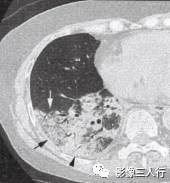

原发性肺淋巴瘤在影像上可呈现肺实质内或肺门旁单发的圆形、卵圆形、分叶状、密度 均匀、边缘清晰的肿块影,其内可见空气支气管征,可累及一叶或一侧肺。继发性肺淋巴瘤 肺内病变包括下面几种。①混合型:肺内病变表现形式多样,可出现多发的肿块结节、斑片 状渗出或实变影以及增粗的支气管血管束,呈两种或两种以上的混合形式存在,可见空气支气管征。见图13。②肿块(结节)型:双侧肺内散在分布的多发性肿块结节,直径在1〜 5cm,多数为类圆形,可见空气支气管征。见图14。③肺炎肺泡型:单侧或双侧肺野分 布的斑片状渗出或实变影,中心密度高,周边密度低,可见空气支气管征。见图15。 ④支气管血管淋巴管型:肺内弥漫性或节段性支气管血管束增粗。⑤粟粒型:表现为双肺弥 漫分布的针尖样大小的阴影,边界清楚,无融合。